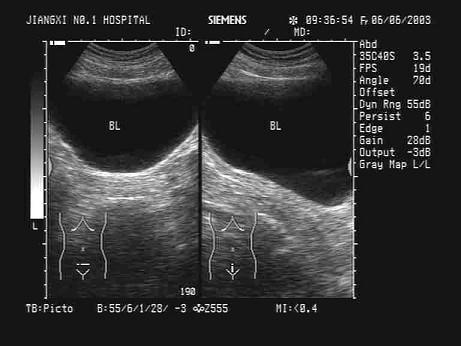

某患者膀胱内超声声像图如下,最可能的诊断为?(?)A.膀胱癌B.正常膀胱C.膀胱结石D.膀胱炎E.膀胱憩室

问题 某患者膀胱内超声声像图如下,最可能的诊断为?(?)

选项 A.膀胱癌 B.正常膀胱 C.膀胱结石 D.膀胱炎 E.膀胱憩室

答案 B